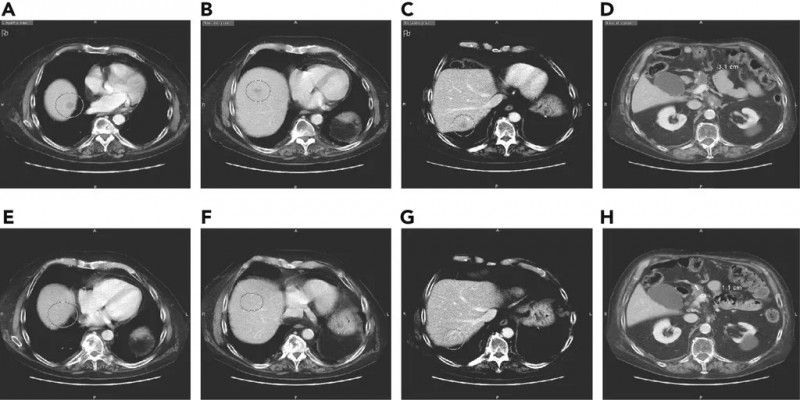

用曲美替尼和羟氯喹治疗移植了胰腺肿瘤的小鼠,结果显示肿瘤一致消退。

用曲美替尼加羟氯喹(T/HCQ)治疗胰腺癌患者导致肿瘤标志物癌抗原19-9(CA19-9)和总体肿瘤负荷减少。